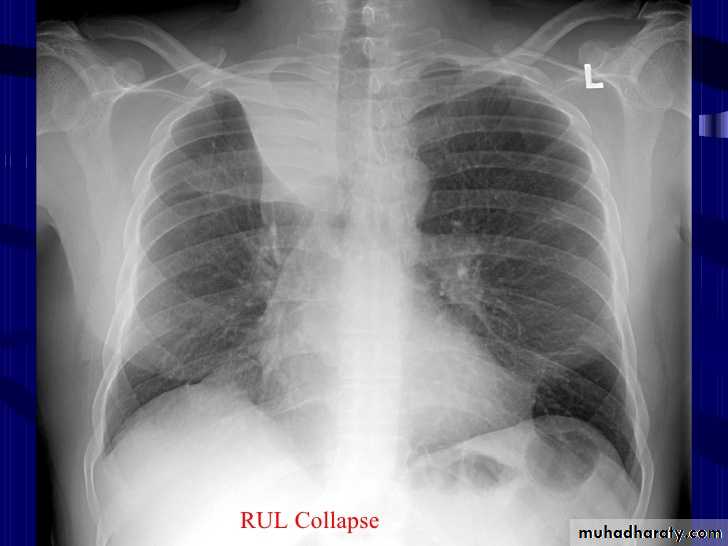

41.RT UL collapse

CXR of adult , PA view shows: Homogenus opacity of right upper lobeElevation of the the horizontal fissure.The trachea is slightly devited to the right

Elevation of ipsilateral hemidiahram, Crowding of the ipsilateral ribs.

42.RT UL collapse (collapse consolidation)

CXR of adult female, PA view shows:Homogenus opacity of right upper lobe (consolidation with air bronchogram)

Elevation of horizontal fissure

Elevation of the right hemidiaphram

Crowding of the ribs on the right side